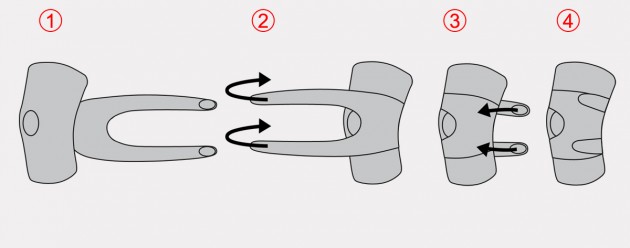

Sposób zakładania